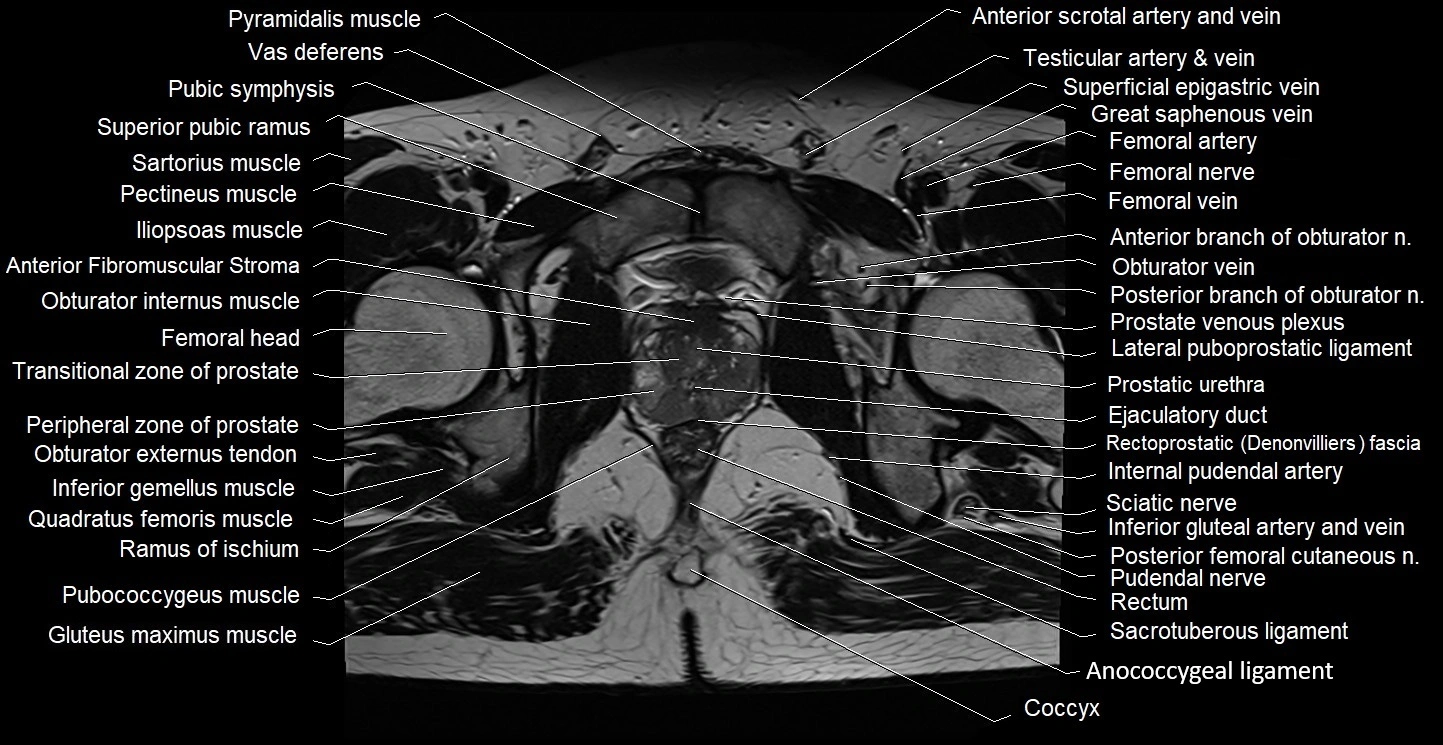

- Anterior Fibromuscular Stroma of prostate

- Anterior division of obturator nerve (Anterior branch of obturator nerve)

- Coccyx

- Ejaculatory duct

- Gluteus maximus muscle

- Iliococcygeus muscle

- Inferior gemellus muscle

- Internal pudendal artery

- Obturator internus muscle

- Peripheral zone of prostate

- Posterior division of obturator nerve (Posterior branch of obturator nerve)

- Posterior femoral cutaneous nerve

- Prostatic urethra

- Pubococcygeus muscle

- Pudendal nerve

- Pyramidal muscle (pyramidalis muscle)

- Quadratus femoris muscle

- Ramus of ischium

- Rectoprostatic fascia (Denonvilliers' fascia)

- Rectum

- Sacrotuberous ligament

- Sciatic nerve

- Transitional zone of prostate